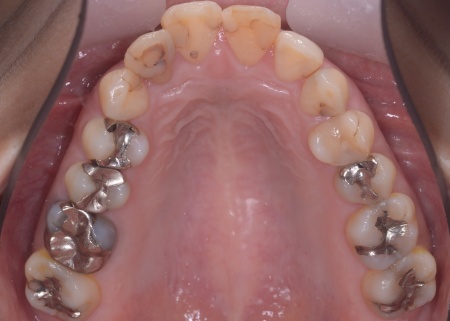

| カウンセリング | 拝見したところ、上前歯が大きく前に出ている上顎前突であり、上下の前歯が噛み合わずに口を閉じても前歯同士が接触しない「開咬(かいこう)」の状態でした。 レントゲン撮影をして詳しく調べた結果、歯の位置だけでなく、骨格的な問題があることが分かりました。 また、前歯で食べ物をうまく噛み切ることができないため、奥歯にも強い負担がかかっているだけでなく、このまま放置すると、奥歯がすり減ったり痛みが生じたりするリスクもあります。 以上のことから、噛み合わせを改善する治療が必要だと診断しました。 |

患者様の場合、骨格的な上顎前突が噛み合わせを乱している主な原因であることから、矯正治療では前歯を後方へ大きく動かすためのスペースを確保する必要があります。 そのため、今回は以下2つの方法を提案しました。 ①抜歯後、アンカースクリューを用いたワイヤー矯正 メリット:骨格的な上顎前突に対応しやすく、前歯を大きく後方へ動かすことができる ②取り外し可能な装置を使用するマウスピース矯正 メリット:装置が透明で目立ちにくく、取り外しができる 以上のメリットとデメリットを丁寧にお伝えしたところ、患者様は①のアンカースクリューを用いたワイヤー矯正を選択されました。 まず、上顎の左右奥歯を抜き、前歯を後方に動かすためのスペースを確保します。 治療の結果、前歯が正しく噛み合うようになり、横顔のバランスも整いました。 矯正治療終了後は、歯が元の場所に戻らないよう上下前歯に保定装置(リテーナー)を装着し、治療を終了しています。 |